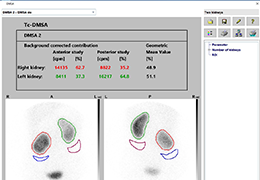

ANYTHINK 经导管主动脉瓣膜置换术分析系统